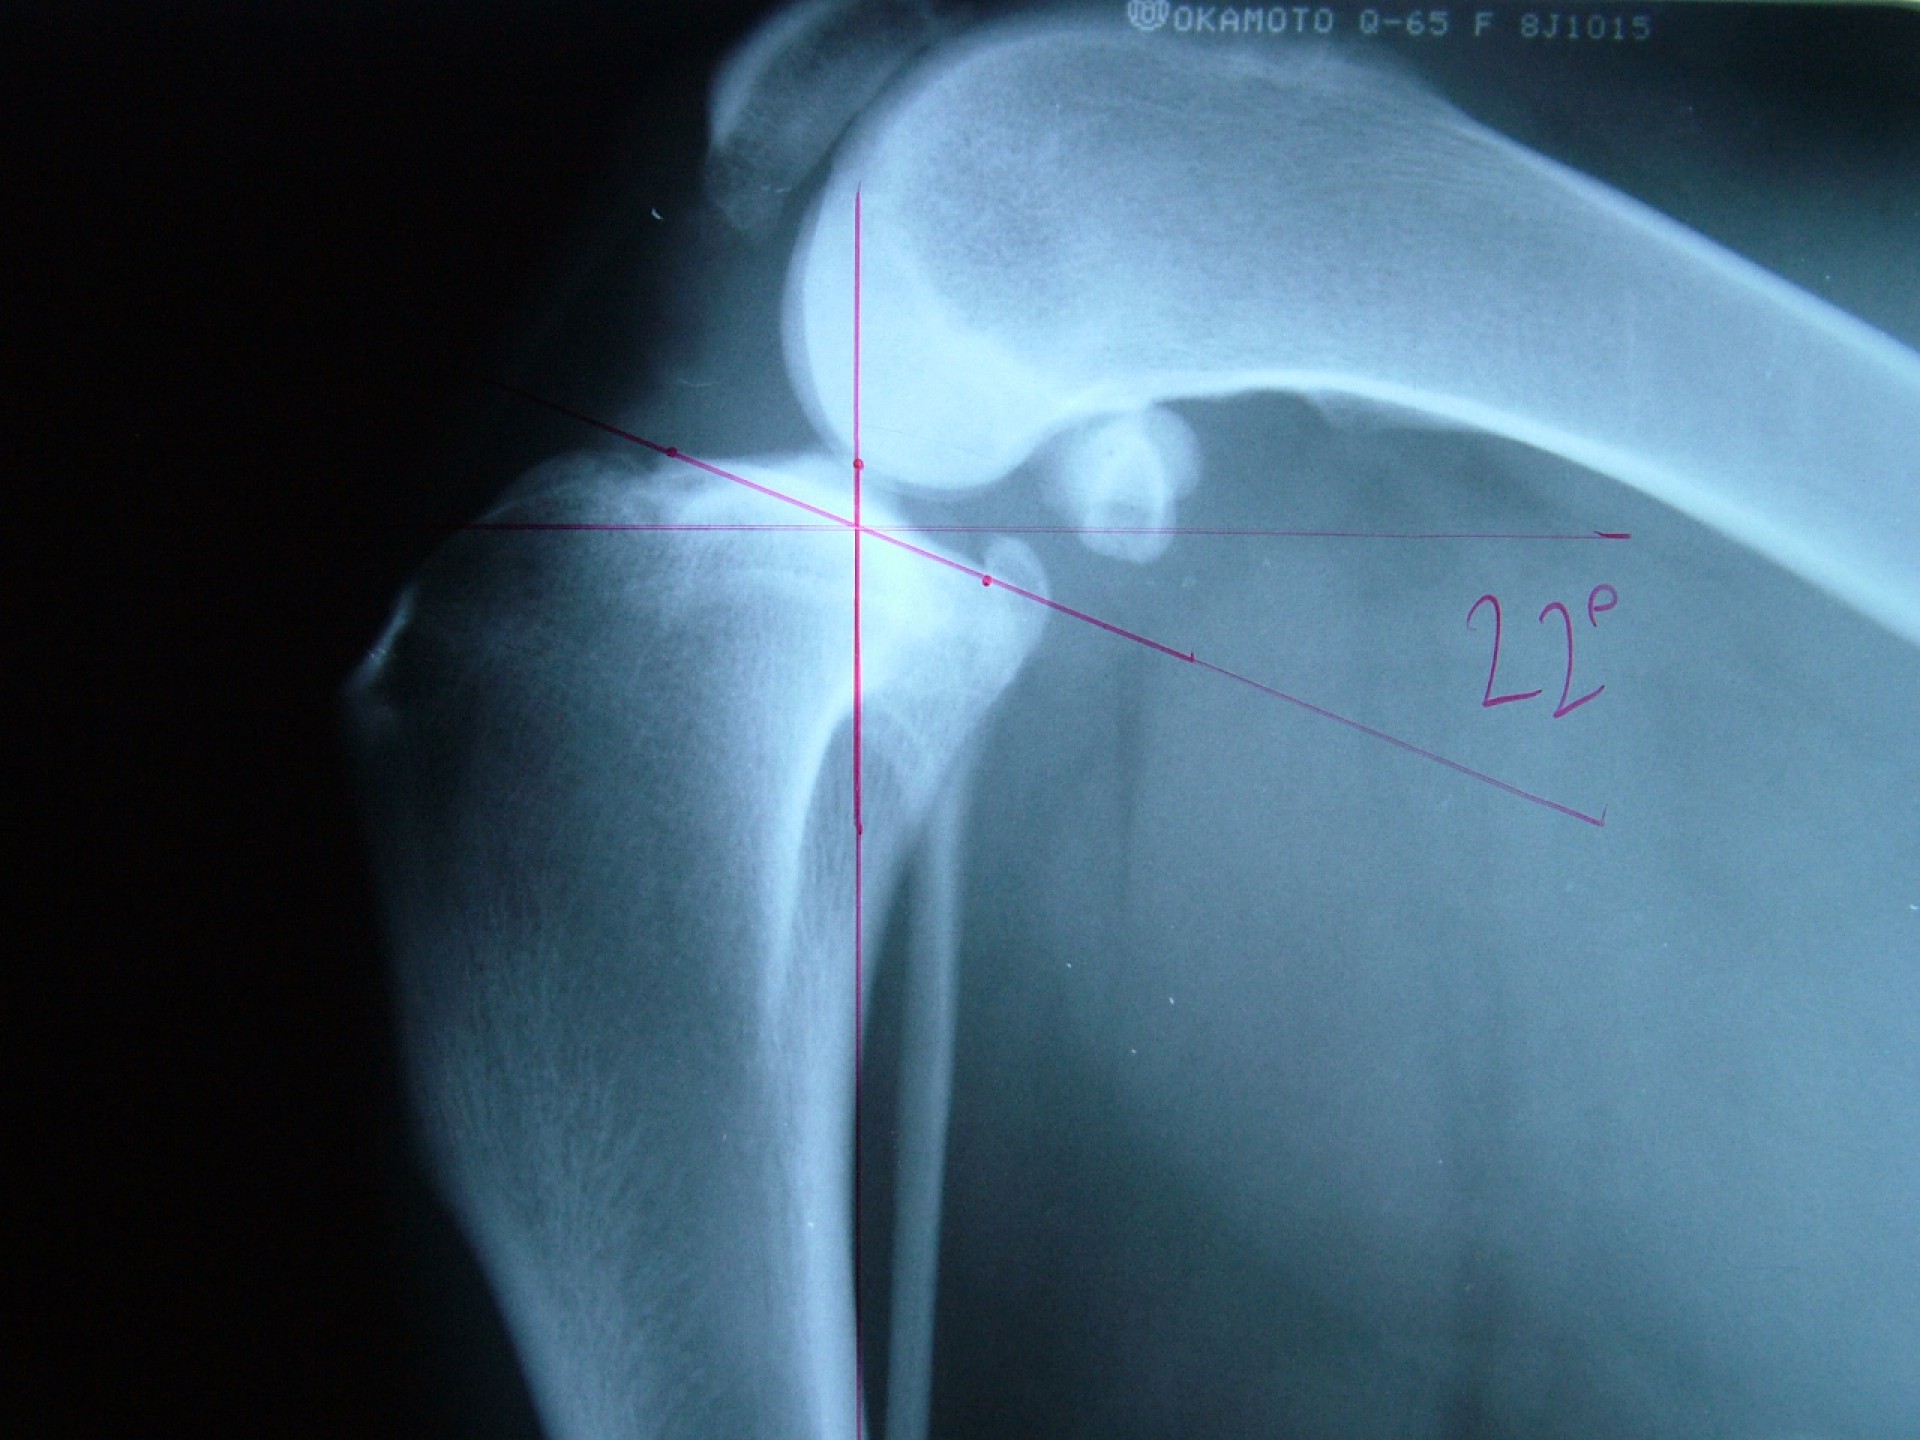

Az utóbbi 25 év egyik legnagyobb előrelépését jelentette a kereszteződőszalag szakadás műtéti megoldásában az amerikai származású Barclay Slocum által kifejlesztett műtéttechnika, mely alapja a szakadásra hajlamosító tényezők és a szalagra ható fizikai erők vizsgálata. Barclay Slocum olyan műtéti technikát dolgozott ki, mellyel a térdízületet az elülső kereszteződőszalagra ható erőkhöz igazítja. Vizsgálatai alapján a sípcsont ízületi felszínének meredeksége (tibia plató szög, tibial plateau angle, TPA) és az elülső kersztezőszalag szakadása között egyértelmű összefüggés mutatható ki. A műtét alapja, hogy a sípcsont ízületi felszínét a sípcsontból kivágott ék, majd azt követő lemezes osteosynthesis segítségével a sípcsont hossztengelyére megközelítőleg merőlegesre állítja be, csökkentve ezáltal a szalagra ható erőket (cranial wedge tibial osteotomy, CWTO).Ezt a technikát továbbfejlesztette: a sípcsonti ízületi felszín szögellésének korrekcióját egy speciális félkör alakú fűrész segítségével, az ízületi felszínt is magába foglaló sípcsonti részlet kivágásával, elforgatásával és rögzítésével oldatta meg (tibial plateau leveling osteotomy, TPLO).